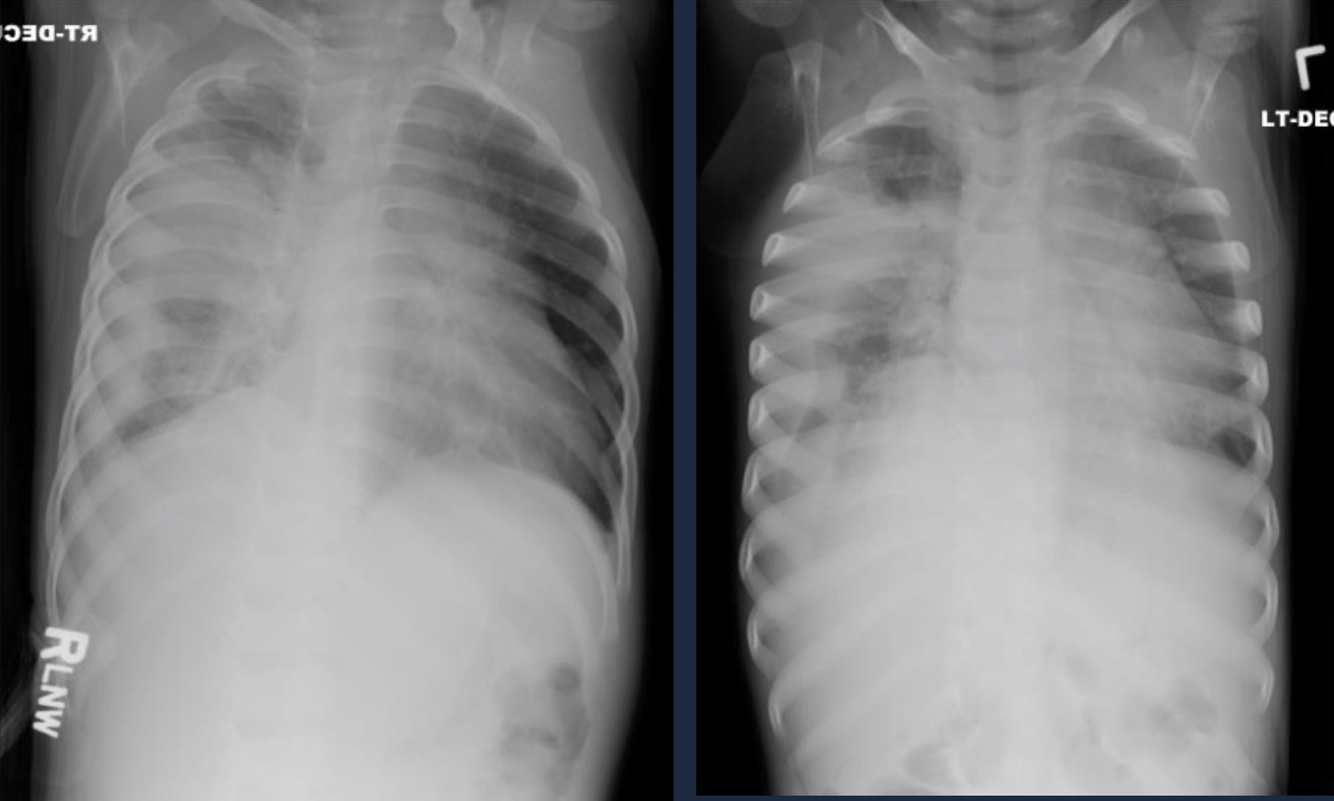

Pleural Effusion

Fluid within the pleural cavity.

CXR: Complicated PNA with pleural involvement.

Empyema

Pus within the pleural cavity.